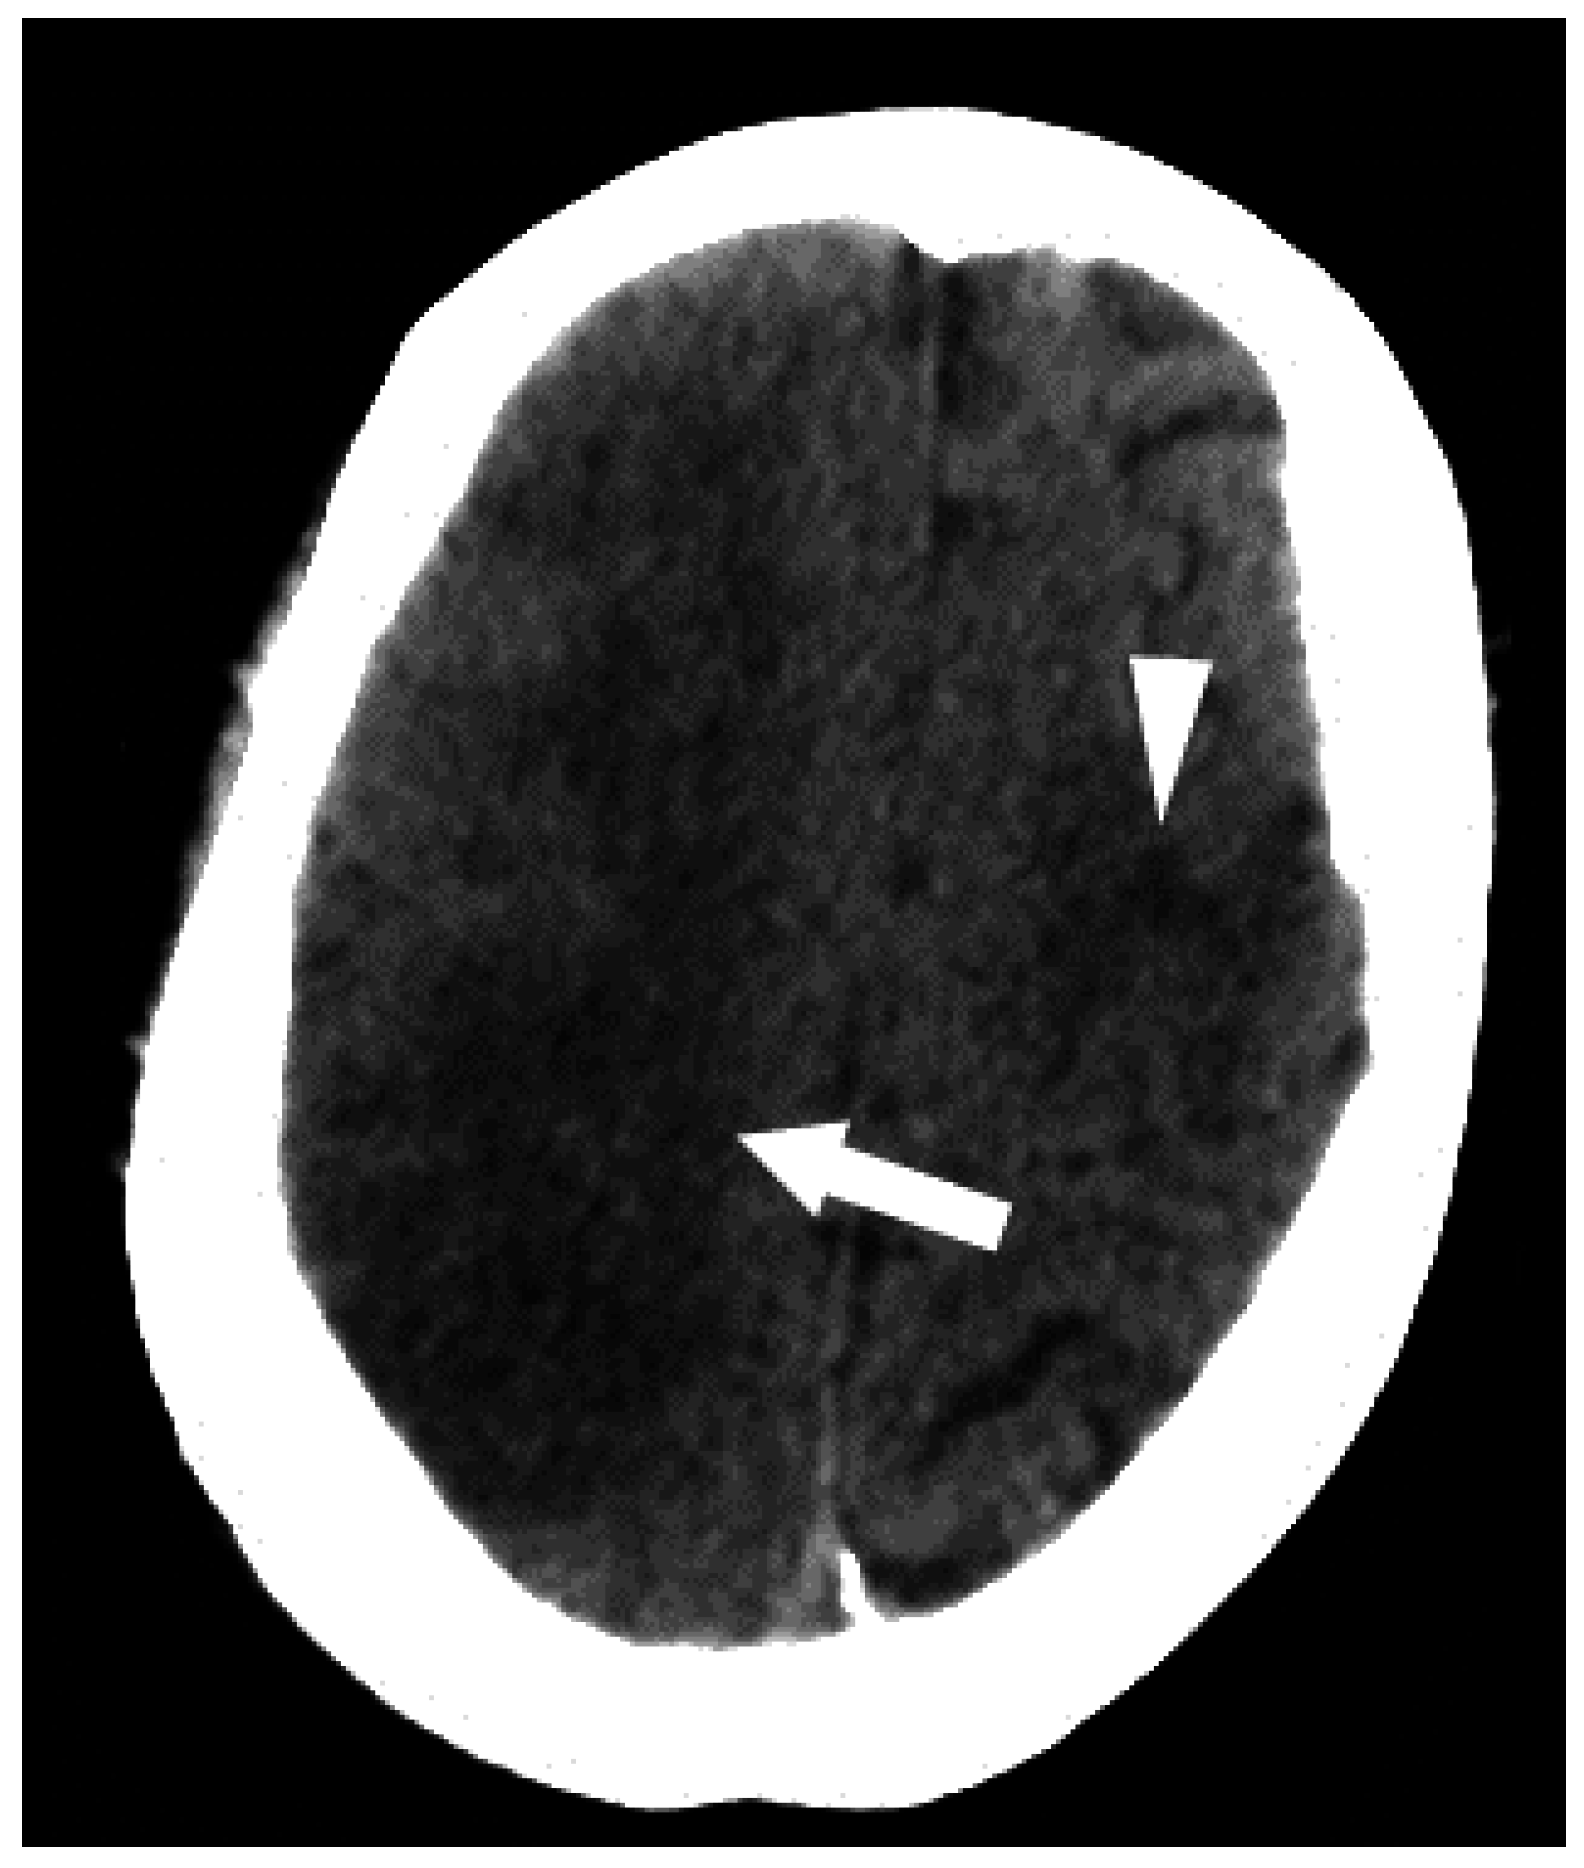

Figure 10.

The successful use of a hyperbaric oxygen therapy (HBOT) is outlined in this case, in which a 69-year-old female with a history of suspected lung cancer underwent a CT-guided lung biopsy at an outside facility (a). During the procedure, the patient suffered a cardiorespiratory arrest. An immediate CT (b) revealed a right pneumothorax (arrow), together with air in the right pulmonary vein (arrowhead). Additional images from the CT scan (c,d), revealed air in the right coronary artery (black arrow), the ascending thoracic aorta (white arrow) and the epidural veins (arrowhead). The patient was initially unresponsive and required cardiopulmonary resuscitation. A non-contrast CT brain (e) was performed, revealing air scattered in the vessels overlying the right cerebral hemisphere (arrowheads). Subsequent MRI of the brain confirmed multiple areas of acute infarction in the right cerebral and cerebellar hemispheres. Axial T2 (f) and DWI (g) images of the brain demonstrated acute areas of infarction in the right cerebellum. The patient required ICU management and HBOT.